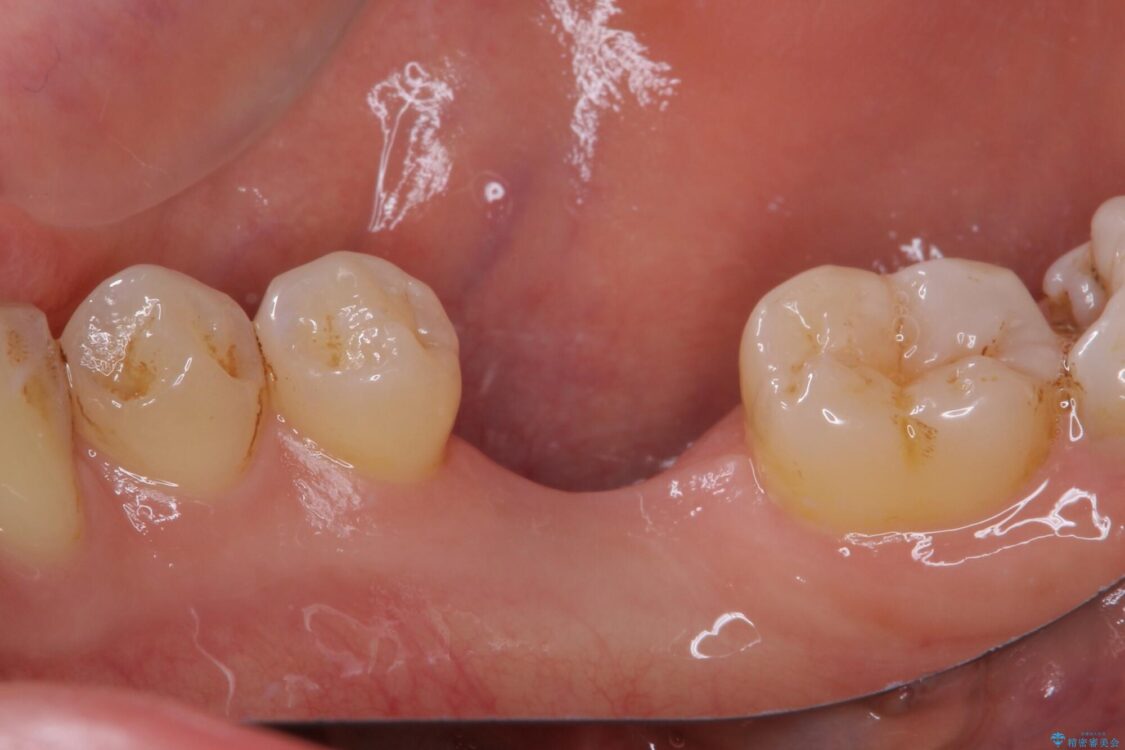

治療前

• 空いている時間を利用して通院 奥歯のインプラント治療 治療前画像